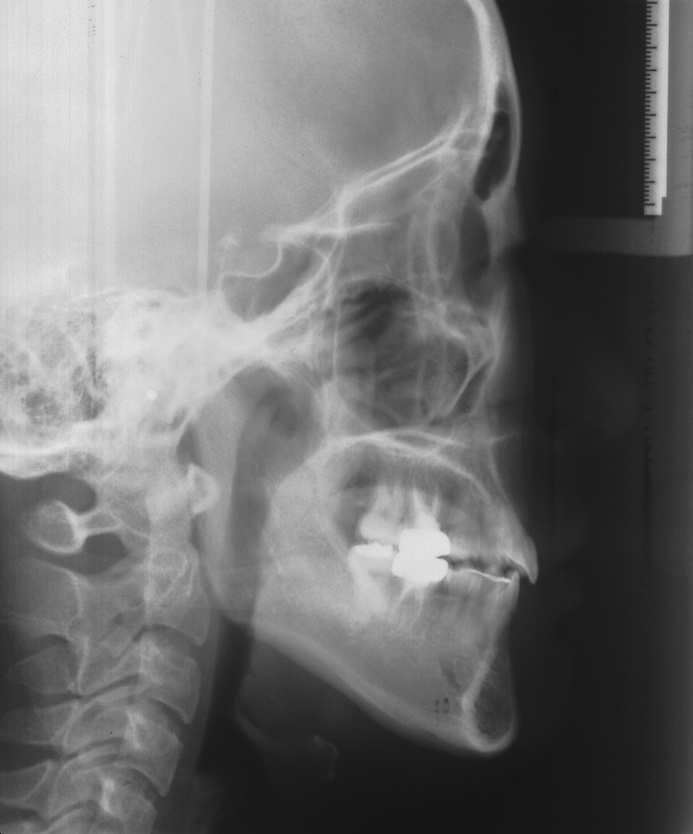

치료 전 사진입니다.